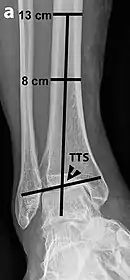

Varus or valgus deformity, if suspected, can be measured with the frontal tibiotalar surface angle (TTS), formed by the mid-longitudinal tibial axis (such as through a line bisecting the tibia at 8 and 13 cm above the tibial plafond) and the talar surface.[24] An angle of less than 84 degrees is regarded as talipes varus, and an angle of more than 94 degrees is regarded as talipes valgus.[25]